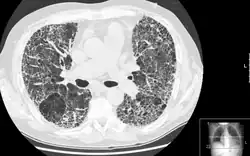

A espirometria permite identificar que se trata de uma doença pulmonar restritiva, mas a radiografia(como raio X) do tórax pode não ser suficiente para encontrar cicatrizes nos pulmões, sendo assim recomendado uma tomografia computadorizada de alta resolução para confirmar a presença da fibrose.[3]